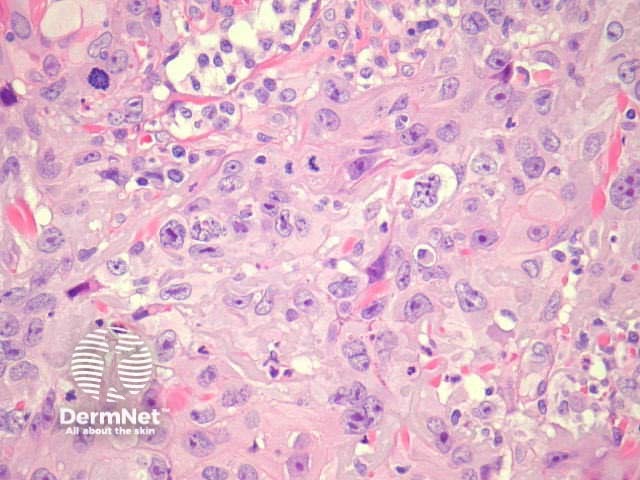

Typical SCC has nests of squamous epithelial cells arising from the epidermis and extending into the dermis (figure 1). The malignant cells are often large with abundant eosinophilic cytoplasm and a large, often vesicular, nucleus. Variable keratinisation (keratin pearls etc) is present (figure 2).

Figure 2